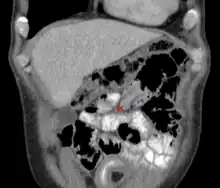

| An intussusception as seen on CT | |

An intussusception is often suspected based on history and physical exam, including observation of Dance's sign. A digital rectal examination is particularly helpful in children, as part of the intussusceptum may be felt by the finger. A definite diagnosis often requires confirmation by diagnostic imaging modalities. Ultrasound is the imaging modality of choice for diagnosis and exclusion of intussusception, due to its high accuracy and lack of radiation. The appearance of target sign (also called "doughnut sign" on a sonograph, usually around 3 cm in diameter, confirms the diagnosis. The image seen on transverse sonography or computed tomography is that of a doughnut shape, created by the hyperechoic central core of bowel and mesentery surrounded by the hypoechoic outer edematous bowel.[10] In longitudinal imaging, intussusception resembles a sandwich.[10] It is also called "pseudokidney" sign because hyperechoic tubular centre is covered by a hypoechoic rim producing a kidney-like appearance.[11]